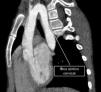

Niña de nueve años con síndrome de DiGeorge fue remitida a nuestra institución por sospecha de arco aórtico derecho. En la exploración física, la paciente presentaba disnea leve, tos y atragantamiento ocasional y palpitaciones cervicales. La tomografía computarizada (TC) cardiaca reveló una anomalía vascular compleja: un arco aórtico derecho que se extendía cranealmente hasta el nivel del ángulo torácico derecho, formando un arco aórtico cervical (AAC) (figs. 1 y 2, Vídeo 1 en Anexo). La primera rama de la aorta era la arteria carótida común izquierda, seguida por la arteria subclavia derecha, la carótida común izquierda y la arteria subclavia izquierda (ASI). La ASI se originaba en un divertículo de Kommerell (fig. 3, Vídeo 2 en Anexo) que, junto con el ligamento ductal, formaba un anillo vascular completo, comprimiendo la tráquea (fig. 3). El AAC es una anomalía congénita poco común en el desarrollo aórtico, presente en menos de uno de cada 10.000 nacidos vivos, caracterizada por un arco aórtico elongado que se extiende hasta los extremos mediales de las clavículas1. Esta condición se asocia con aneurismas (hasta un 20% de los casos), coartación aórtica, anomalías cardiacas congénitas, síndrome de Turner y de DiGeorge1,2. Dada la presencia de un anillo vascular completo con sintomatología obstructiva asociada, se indicó tratamiento quirúrgico3.